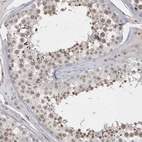

Immunohistochemical staining of human testis shows moderate nuclear positivity in seminiferous duct cells.